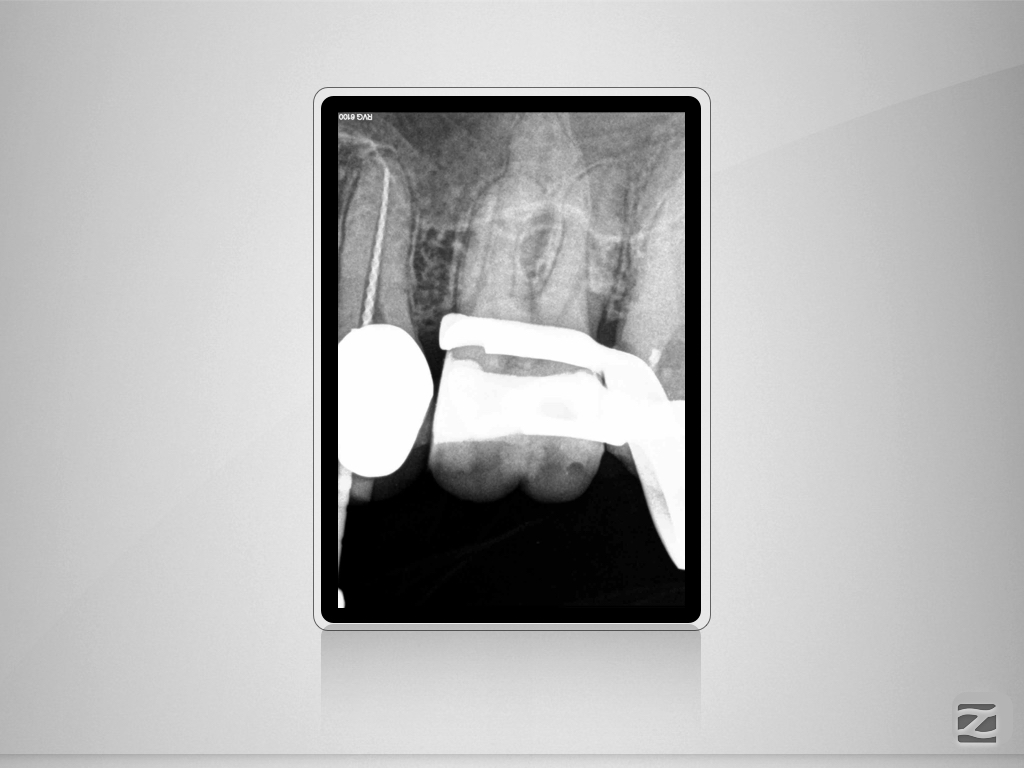

15D.004

Therapieplanung in 3D